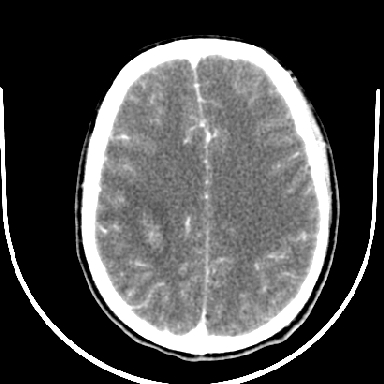

标题: CT6056:脑出血(血管畸形?) [打印本页]

标题: CT6056:脑出血(血管畸形?)

m 40突发头痛左侧偏瘫3小时

考虑高血压性脑出血,依据:

1是高血压性脑出血的好发部位,形态呈肾形,是高血压性脑出血的常见形状

2增强时占位效应加重了,考虑出血还没有停止

3病灶周围水肿不是太厉害,一般肿瘤出血水肿多非常明显

4病灶周围的‘软组织’影没有明显的强化

5至于脑血管畸形引起的出血,暂时没有看到明显的畸形血管影,也不太支持

支持右侧基底节脑出血

右侧基底节区脑出血.

支持右侧基底节区(主要为外囊区)原发性脑出血。

另附部分资料:“血液溢出血管外形成血肿,其内含有大量血红蛋白、血浆白蛋白,球蛋白,因这些蛋白对x线的吸收系数高于脑质,故ct呈现高密度阴影,ct值达40~90h,最初高密度灶呈非均匀一致性,中心密度更高,新鲜出血灶边缘不清。基底节区血肿多为“肾”型,内侧凹陷,外侧膨隆,因外侧裂阻力较小,故向外凸,其它部位血肿多呈尖圆形或不规则形”

术中抽出40ml陈旧血液,血肿底部似见一条索血管影